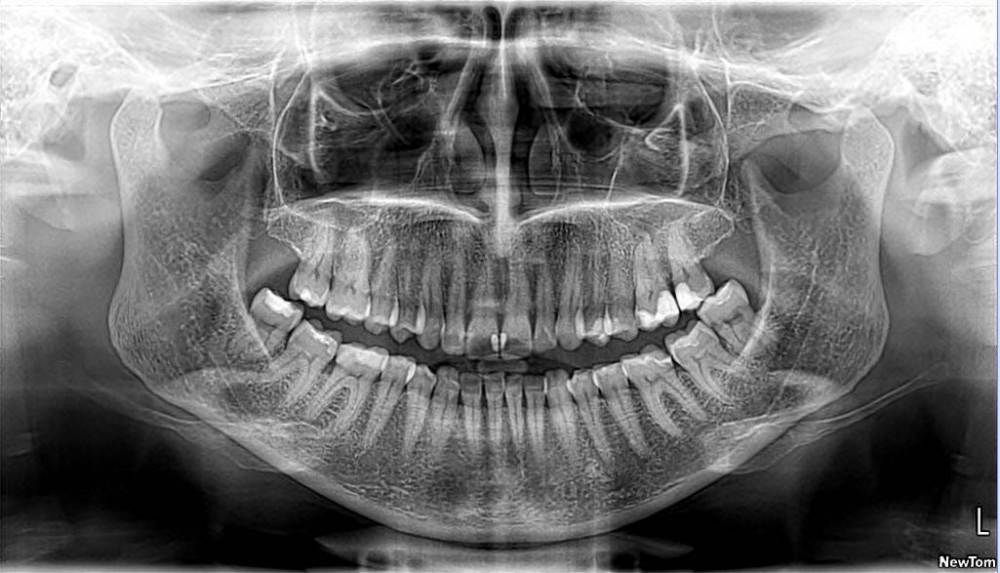

АннаК Опубликовано 1 марта, 2022 Поделиться Опубликовано 1 марта, 2022 Добрый день! Прошу совет: есть глубокий кариес на левой верхней шестерке (на снимке она справа). Пломбу ставили 14 лет назад. Уже тогда врач собирался депульпировать зуб, но после вскрытия сказал, что можно рискнуть и сохранить корни. После процедуры чистки ультразвуком несколько месяцев назад появился скол в верхней части, боль при надкусывании, чувствительность. Через несколько месяцев боль прошла, хотя скол стал больше. Сейчас чувствительности нет, боли нет. На приеме врач сделал прицельный снимок на пленку и сказал, что под пломбой кариес и показано депульпирование с установкой коронки. На мой вопрос про "зуб же еще не болит" сказал, что есть небольшой шанс, что удастся сохранить корни и обойтись накладкой, но ясно встанет после вскрытия. Дело в том что это маленькая стоматология, поэтому если шанс сохранить зуб не реализуется, то возможности лечить каналы под микроскопом у этого врача не будет. Можно ли сохранить этот зуб? Стоит ли искать другую стоматологию с возможностью лечения под микроскопом? Прилагаю ортопантомограмму, поскольку прицельный снимок на пленке. Врач ее еще не видел, поскольку я делала ее во внешнем центре, но сказал, что она будет не менее информативна, чем прицельный снимок. Буду благодарна за совет. Ссылка на комментарий

wladdX Опубликовано 1 марта, 2022 Поделиться Опубликовано 1 марта, 2022 Похоже, что шанс обойтись без депульпирования отсутствует. На мой взгляд, пульпа уже погибла. Ссылка на комментарий